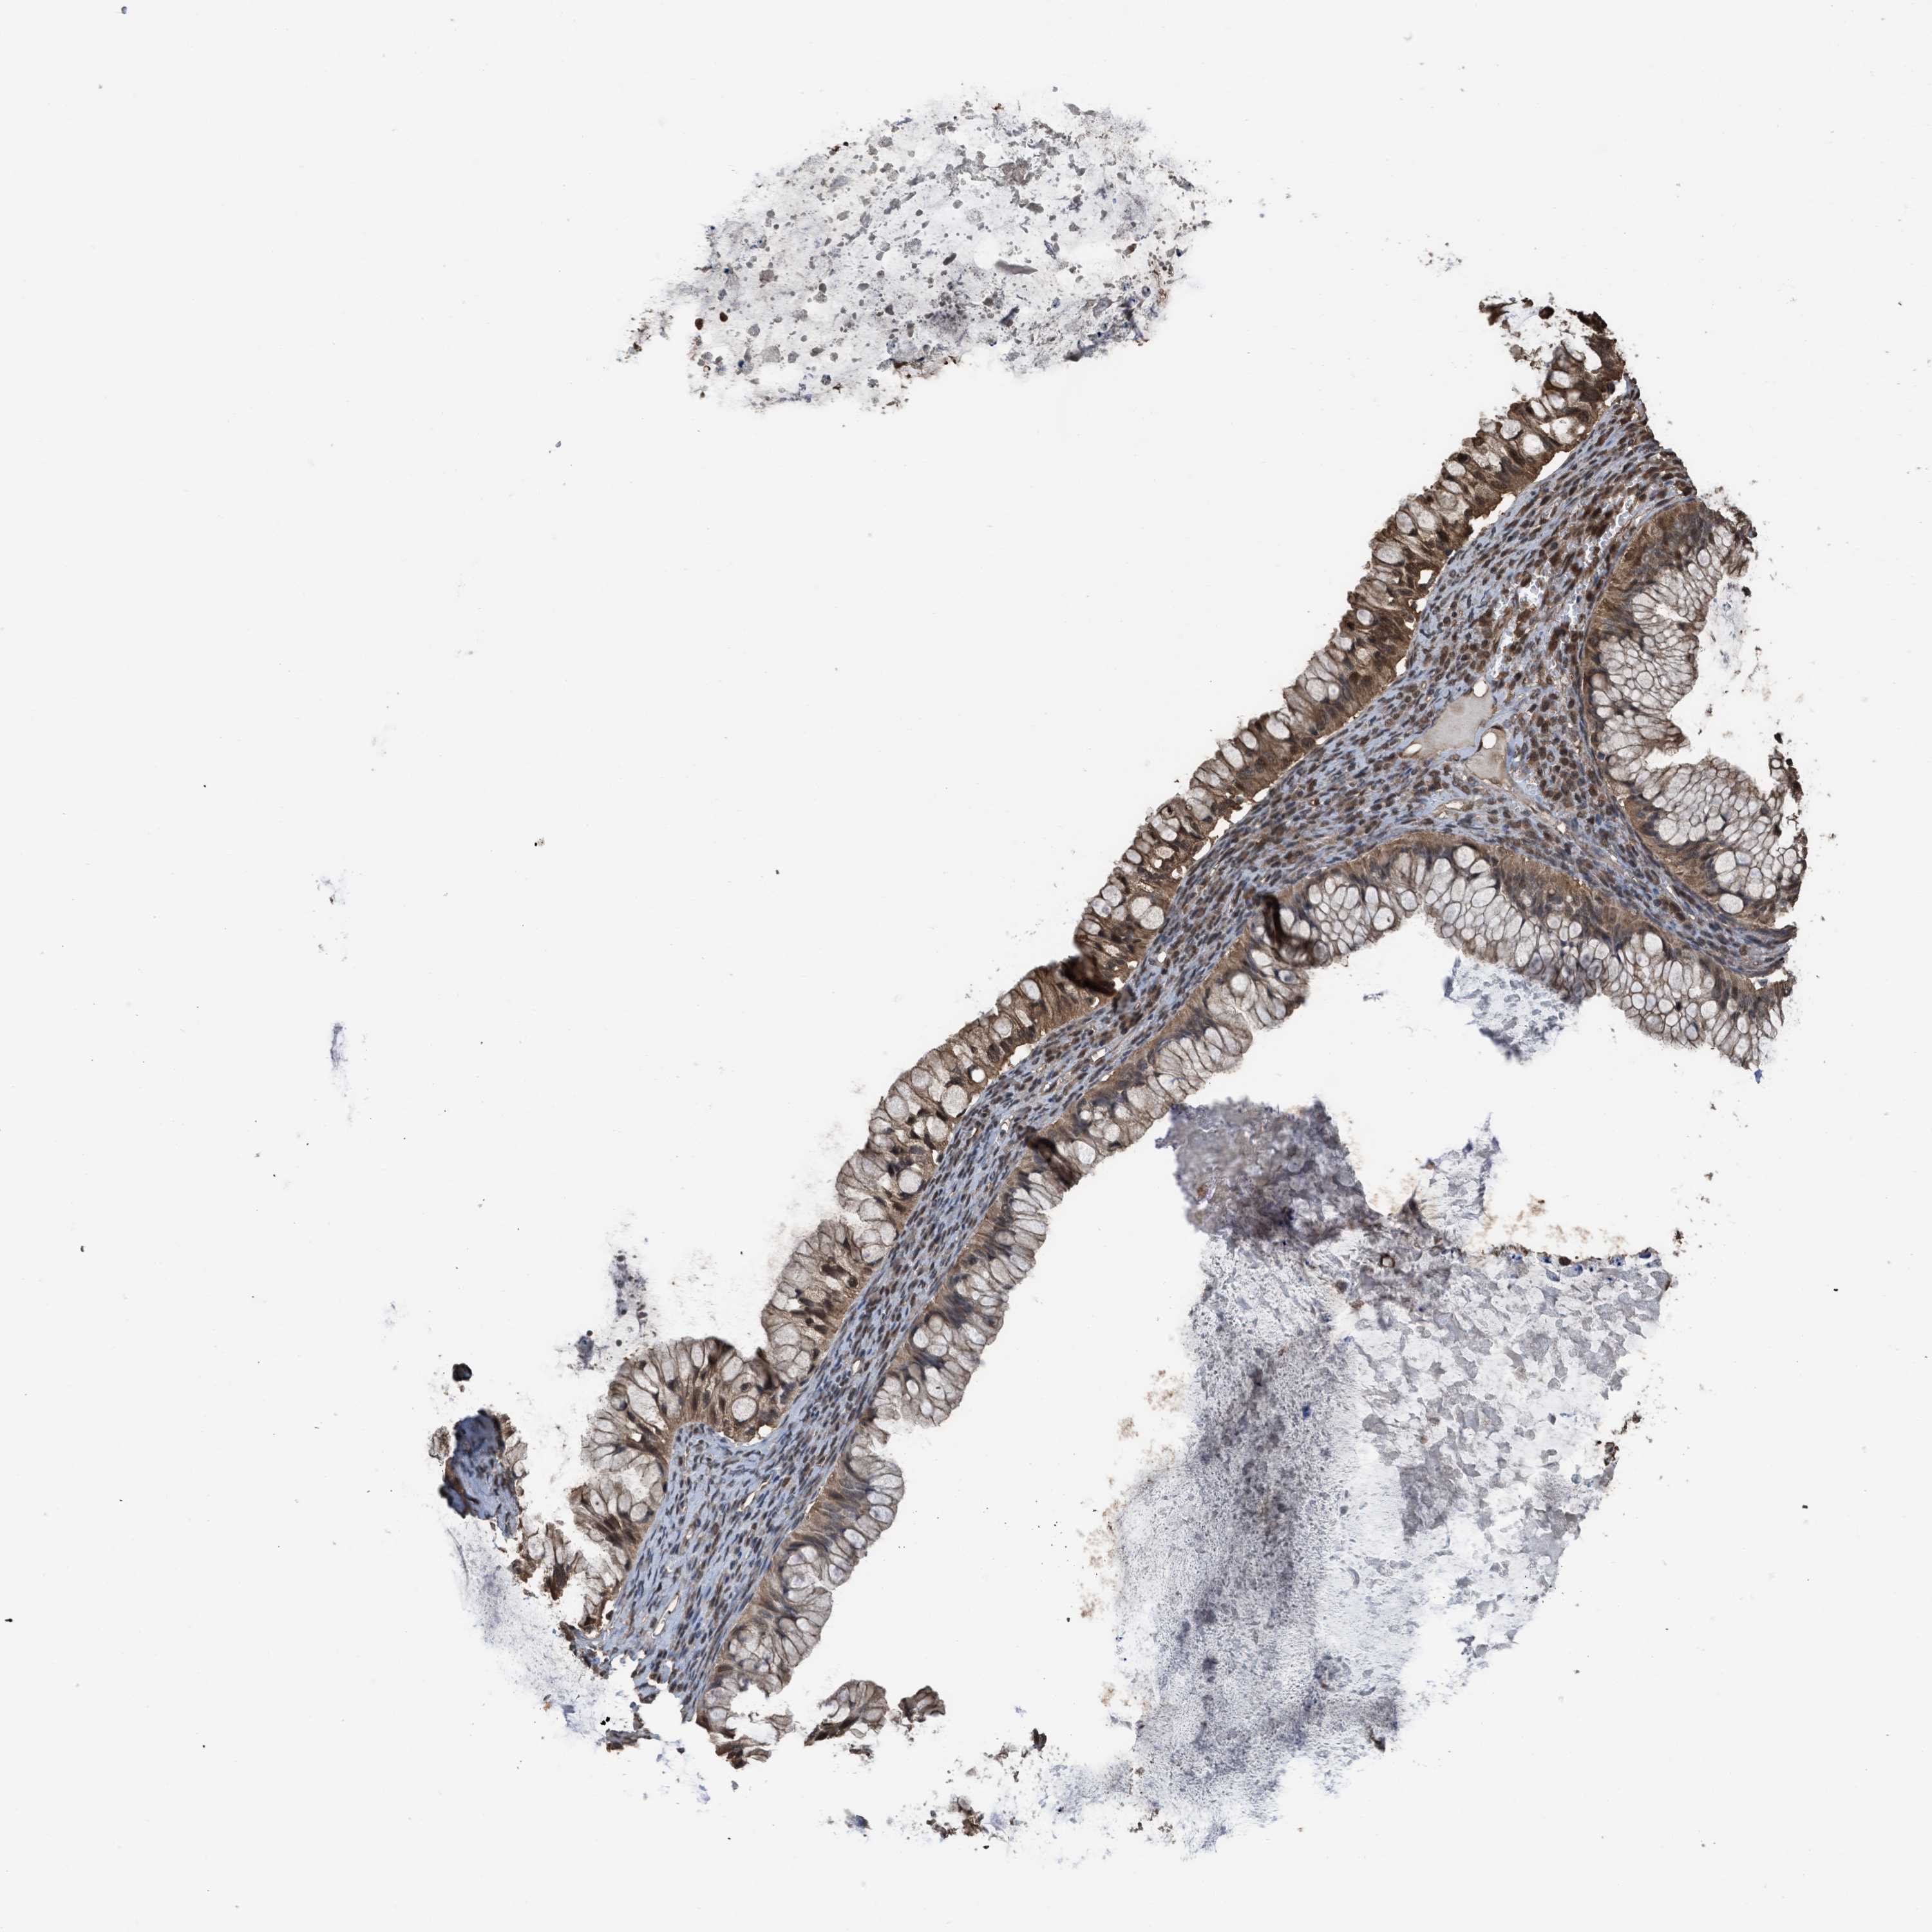

OVARIAN CANCER - Protein expressioni

A mouse-over function shows sample information and annotation data. Click on an image to view it in a full screen mode. Samples can be filtered based on level of antibody staining by selecting one or several of the following categories: high, medium, low and not detected. The assay and annotation is described here.

Note that samples used for immunohistochemistry by the Human Protein Atlas do not correspond to samples in the TCGA dataset.

Antibody stainingi

Antibody staining in the annotated cell types in the current human tissue is reported as not detected, low, medium, or high, based on conventional immunohistochemistry profiling in selected tissues. This score is based on the combination of the staining intensity and fraction of stained cells.

Each image is clickable and will lead to virtual microscopy that enables deeper exploration of all samples and also displays staining intensity scores, fraction scores and subcellular localization as well as patient and tissue information for each sample.

Antibody HPA026918

Antibody CAB013274

Antibody CAB018389

Staining

High

Medium

Low

Not detected

Carcinoma, NOS

Cystadenocarcinoma, serous, NOS